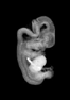

Animations

MRI Slice Selector